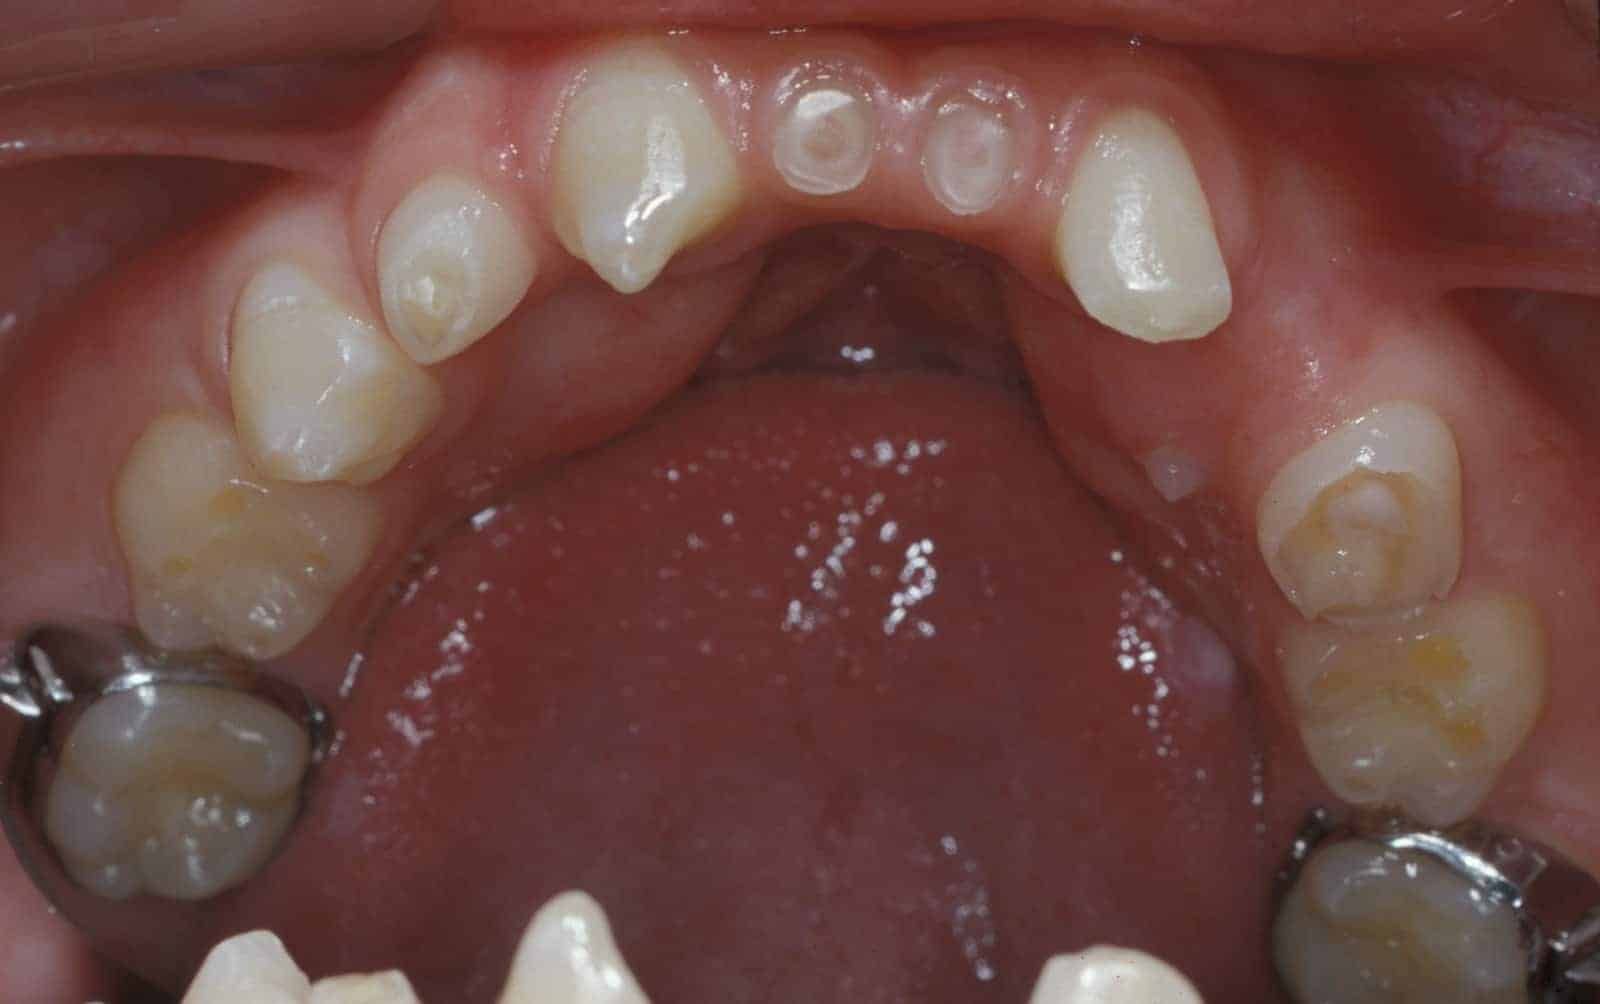

Before: Patient is missing 19 adult teeth. Treatment to replace the missing teeth began at age 12 and was completed at age 21. Treatment involved a team approach, with an Orthodontist, Oral and Maxillofacial Surgeon, and Prosthodontist (Dr. Leopardi) heading the team. Orthodontic therapy was performed first to move existing adult teeth to allow for implant tooth replacement therapy in missing teeth sites (tooth-implant-tooth relationship).